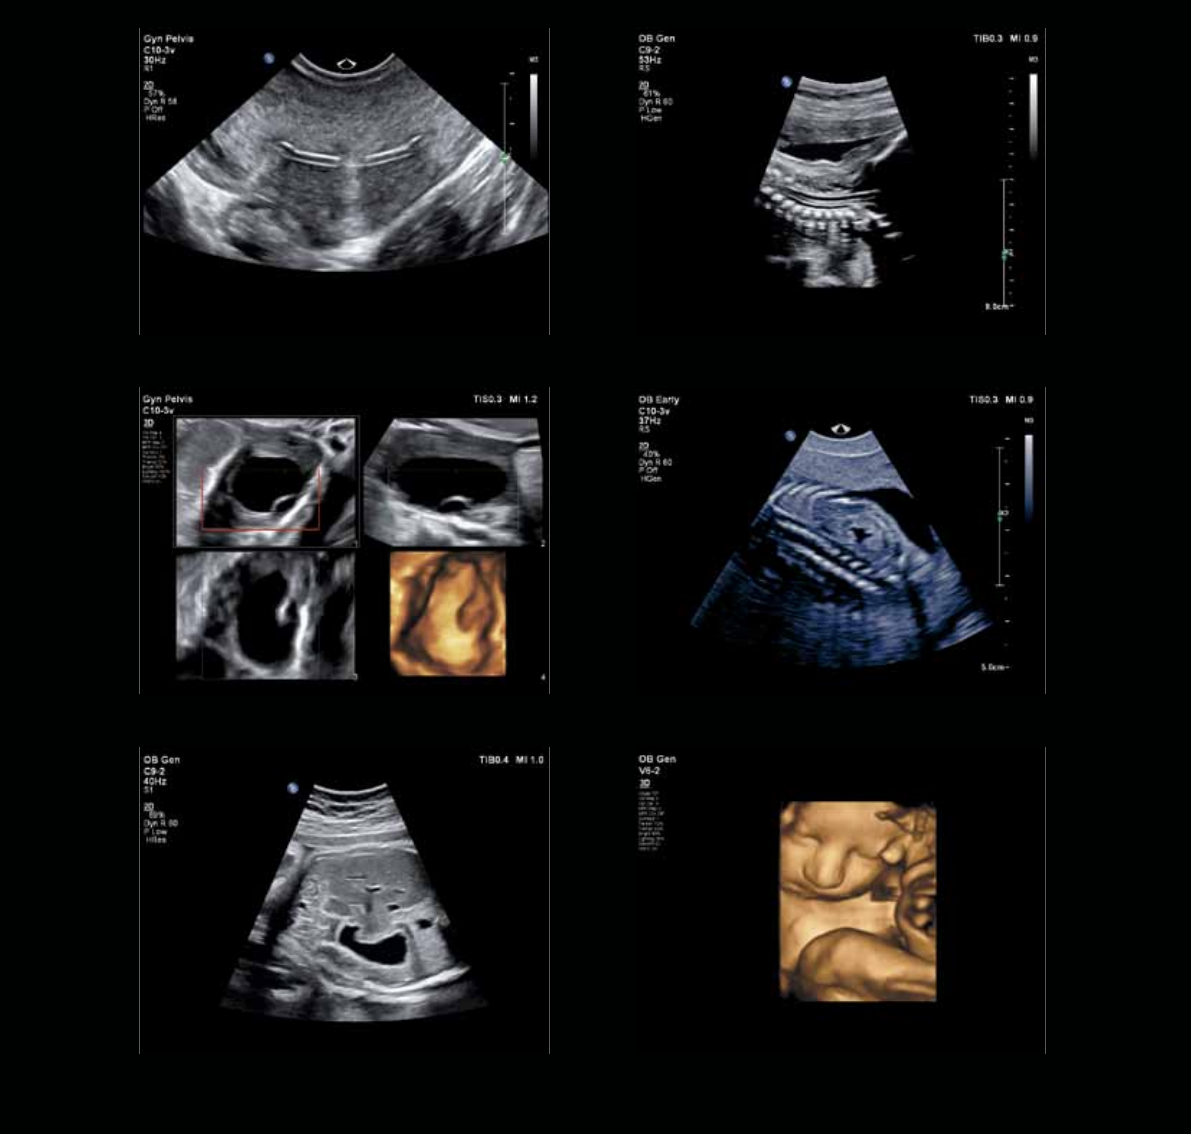

Intrauterine device Fetal spine

13-week fetal kidneyOvarian cyst

34-week gestationFetal abdomen

Automation supports

the way you work

This powerful architecture also supports automation designed to aid

your workow and increase your condence in the most challenging

exams, such as rst trimester or fetal heart.